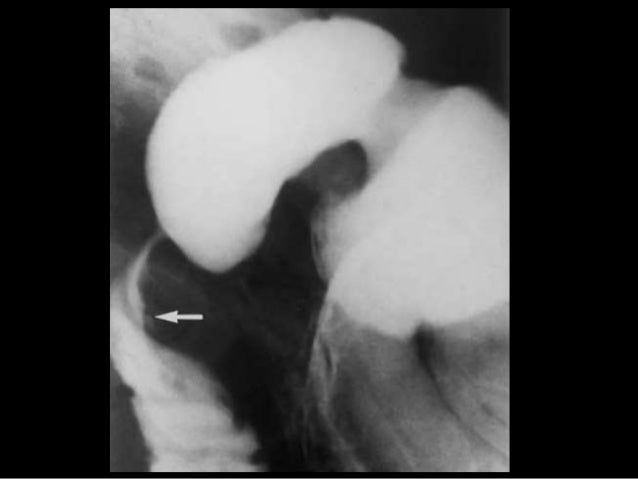

УЗИ диагностика кольцевидной поджелудочной железы: что важно знать